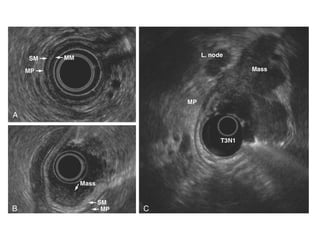

Endoluminal Ultrasonography

Diagnostic

Staging of gastric

cancer

(Depth of invasion,

lymph nodes, ascites,

adjacent structures)

Using flexible endoscope with a 7.5 to

12 megahertz transducer

Stomach is filled with water to provide

acoustic window

Can detect perigastric and celiac lymph

nodes 5 mm or greater in size

Disadvantages: operator dependant,

lymph nodes smaller than 5 mm with

metastasis not detected

Muscle is hypoechoic